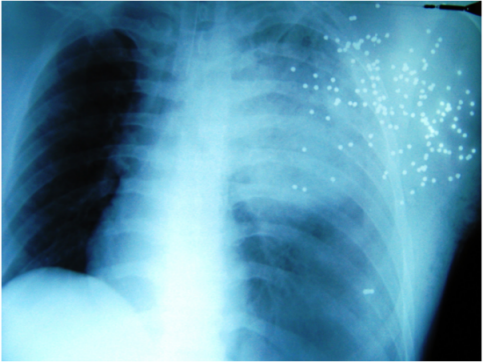

Special complications of shotgun injuries are “projectile embolizations”, which can lead through vessel obstruction to gangrene of lung, cerebral infarction or to vessel arrosion combined with a massive bleeding [5], [6], [7], [8]. To avoid these fatal consequences, a surgical resection is always indicated [5], [8]. Upon arrival at the emergency trauma room the X-ray of the thorax (Figure 4 [Fig. 4]) provides important information. Intraabdominal bleeding increases lethality dramatically [9]. To exclude a pericardial tamponade or intraabdominal bleeding (“free fluid in the abdominal cavity”) a sonography (FAST) of abdomen and thorax should be performed simultaneously [3], [10], [11], [12] [13]. The route of the ricochets determine the operative access [9], [12], [14]. For example in cases of heart or abdominal injuries, median sternotomy and median laparotomy are performed while in cases of a ipsilateral lung injury a lateral thoracotomy is performed [12], [14]. If the patient is haemodynamically stable, whole-body CT scan is the best diagnostic tool for detection of foreign bodies [4]. If there is not enough time for this investigation, because the patient is haemodynamically unstable, the whole-body CT scan has to be performed postoperatively. In cases of emergency thoracotomy [15], the FAST can be performed in the operating room during anesthetic induction. Additionally, the detection of metallic foreign bodies can be performed via C-arm X-ray to determine the operative access on time [6], [14]. After thoracotomy, the immediate bleeding control is decisive. The disconnection of the lung hilum is the fastest control opportunity (because due to the massive bleeding the situs is confusing) and the risk of air embolism is reduced by this maneuver [6], [12], [14], [16]. After suction of blood (most suitable is the cell saver for blood recovery [17]), the selective disconnection of hemorrhage sources follows, e.g. from the lung parenchyma or big vessels. The hilum clamp should be used only for a short time because acute right heart failure could occur. The dimension of resection of the lung has to be limited, because lethality increases proportionally to the loss of parenchyma. A pneumonectomy for example is related to a 80% higher mortality [2], [16], [18], [19], [20]. With a so-called “tractotomy” the shot channels could be opened and supplied with a minimal loss of parenchyma [3], [6], [9], [11], [16], [18]. Essentially, even in cases of no external damage, a pericardiotomy has to be performed to exclude a myocardial lesion [6], [12], [15]. This maneuver is also important if a direct bimanual cardiac massage is necessary [6]. Normally the patients with such massive traumata develop the so-called “deadly triad” [21], [22] with metabolic acidosis, hypothermia, and disseminated intravascular coagulopathy with consequential diffuse bleeding, which is only manageable through intrathoracal tamponade (“packing”) [14], [16], [21], [22], [23]. After these damage control measures the thoracic muscles are only adapted and the pleural cavity is left open [24], [25] to prevent thoracic compartment syndrome [26]. Afterwards, the patient is stabilized in the ICU with correction of the pathophysiological derangement (acidosis, hypothermia and coagulopathy). In a second-look operation (SLO) after 24 to 48 hours [12], [22] the tamponades can be removed and the thorax can be closed definitively. Because of the massive tissue destruction and the inclusions of contaminated metallic and powder fragments, the wounds have to be debrided carefully [2], [27], [28] combined with a high-sensitive antibiotic treatment [3], [27]. An extensive exploration of the wound is also necessary because inclusions of clothes or plastic fragments can not be detected via X-ray. The placement of a vacuum-assisted closure dressing has proven especially valuable [28], [29], [30], leading to quicker wound cleansing and wound granulation compared to traditional wound dressings [28]. That is why remaining defects can be covered more quickly with mesh graft transplantation [27], [28], [29], [30].

Figure 4: X-ray: multiple pellets in the chest